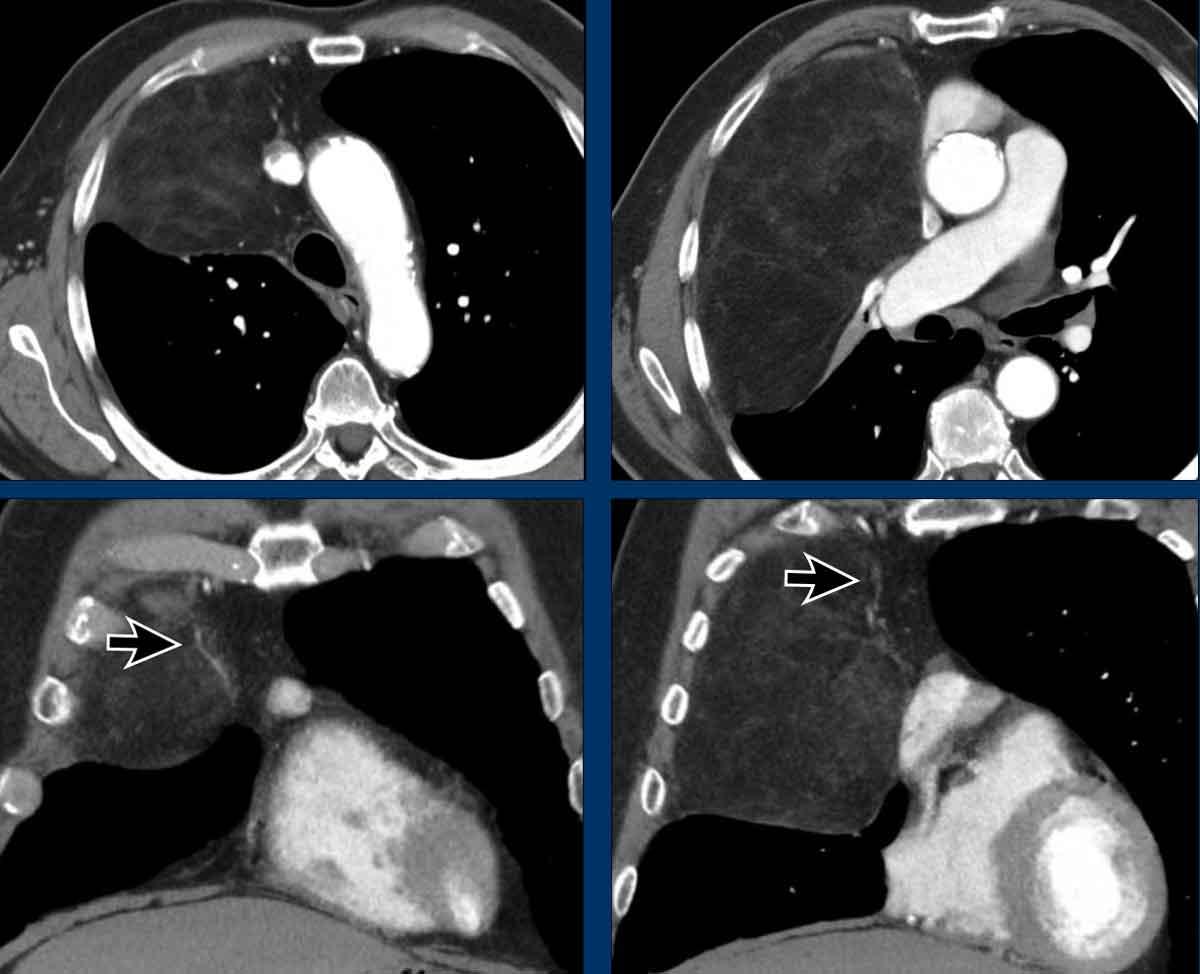

Các hình ảnh này của một bệnh nhân đã được phẫu thuật cắt bỏ thymoma.

Trên phim chụp theo dõi bên trái, phát hiện một tổn thương di căn màng phổi.

Lưu ý rằng nhìn lại, đã có một tổn thương màng phổi rất nhỏ trên phim chụp trước phẫu thuật.

Bài học rút ra là khi nghĩ đến thymoma, cần phải khảo sát màng phổi một cách hết sức tỉ mỉ.

“Bạn chỉ tìm thấy những gì bạn đang tìm kiếm”.

Có một khối đặc ở trung thất và các tổn thương màng phổi.

Thảo luận

Các tổn thương màng phổi chỉ xuất hiện ở bên phải, đây là đặc điểm điển hình của di căn màng phổi kiểu “nhỏ giọt” (pleural drop metastases) của thymoma.

Chúng là kết quả của sự xâm lấn trực tiếp vào màng phổi, không phải di căn theo đường máu, và chỉ xuất hiện ở một bên.

Tiếp tục xem PET…

Hình PET cho thấy khối ở trung thất và nhiều tổn thương di căn màng phổi chỉ ở bên phải.